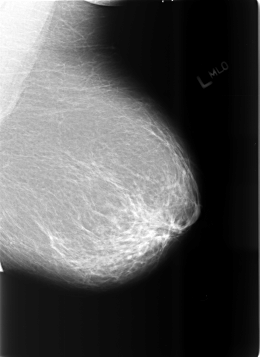

B_3465_1.LEFT_MLO

B_3465_1.LEFT_CC

LEFT_MLO LINES 5704 PIXELS_PER_LINE 4152 BITS_PER_PIXEL 12 RESOLUTION 50 NON_OVERLAY